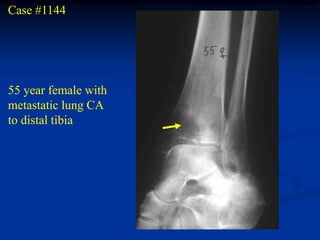

Case #1144

55 year female with

metastatic lung CA

to distal tibia

Chest x-ray showing primary lung CA